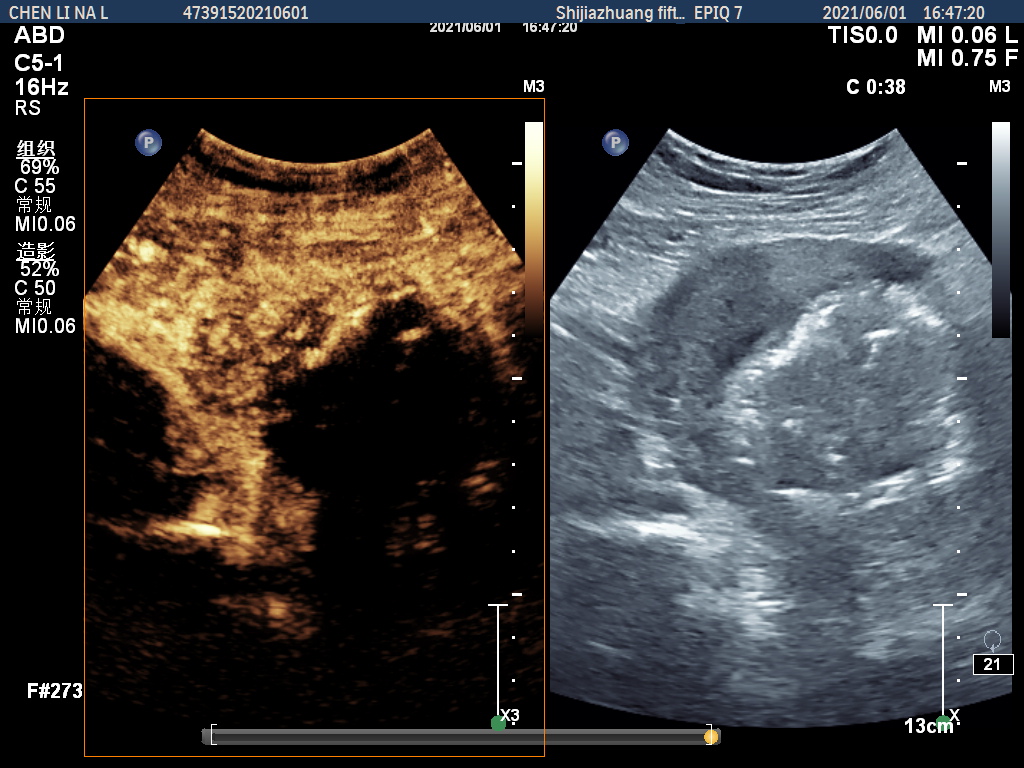

图2 子宫肌瘤微波消融术后超声造影显示瘤体内无造影剂